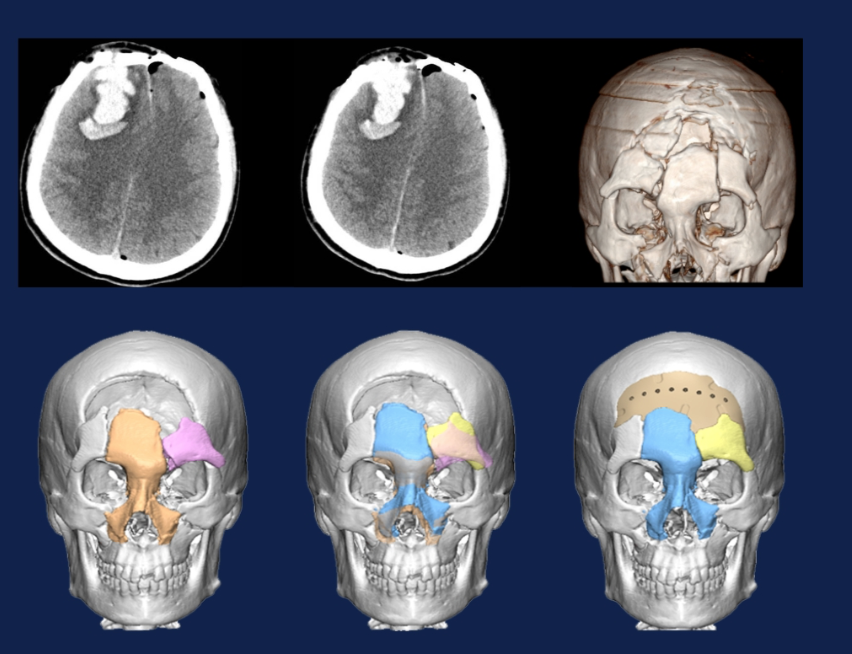

复杂开放性颅脑外伤的治疗和外观重建